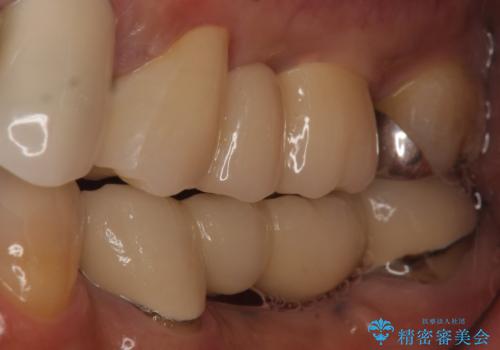

- 昔治療した左上56の延長ブリッジをきちんと治療しなおしたいといらっしゃった方の症例です。

古いブリッジを除去後、オールセラミッククラウンによる補綴を行いました。

今回用いたオールセラミッククラウンは、ジルコニアフレームという白い素材の上にセラミックを盛っているため審美性が非常に高いのが特徴です。

またジルコニアは人工ダイヤモンドの材料にも使われているほど高い強度を持っており、そのためオールセラミッククラウンは審美性だけでなく、奥歯やブリッジの補綴も可能とするクラウンです。